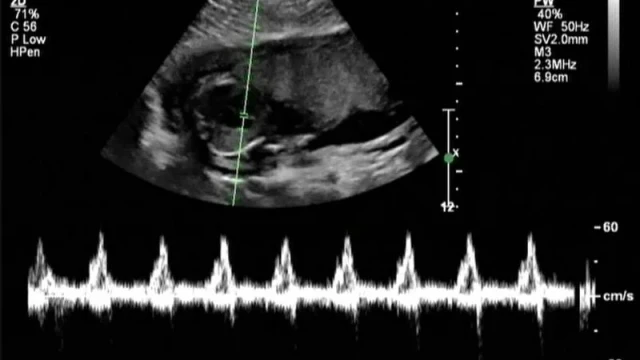

The placenta-on-a-chip model was fabricated and meticulously tested to simulate the transport of NTX/6β-naltrexol from the maternal channel to the fetal channel. From the fetal channel, the transported NTX/6β-naltrexol was collected and directed toward cultured N27 neural cells. The neural cells were then evaluated for gene expression and cell viability following exposure to the pharmaceutical agents.

During the study, the mean fetal concentrations of NTX and 6β-naltrexol over an 8-hour interval were recorded. The findings provide critical insights into how NTX/6β-naltrexol affects embryonic brain cells, further supporting the need for ongoing research in this area.

By utilizing advanced liquid chromatography/mass spectrometry (LC-MS), the study effectively analyzed the transport of clinically relevant concentrations of NTX and 6β-naltrexol.